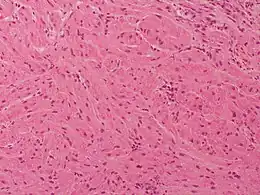

Description de l'image Granular cell tumor Case 174 (5600864519).jpg.

C'est un schwannome à cellules granuleuses. Le diagnostic sera fait par l’histologie (cytoplasme micro-granuleux) pour le différencier d'un histiocytofibrome.